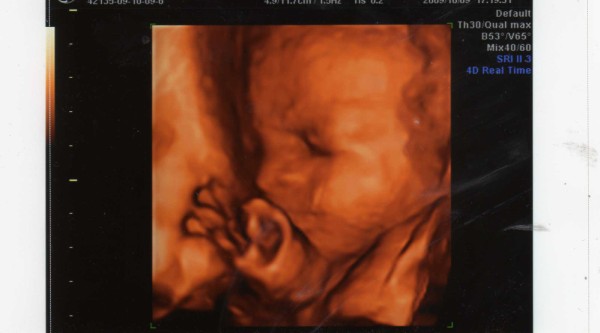

Ultrahangon minden rendben volt, Tesóka nagyon jól van! Holnap feltöltöm a képet a gépre, és akkor megmutatom, bár mélyen a placentába volt az arca a Drágámnak